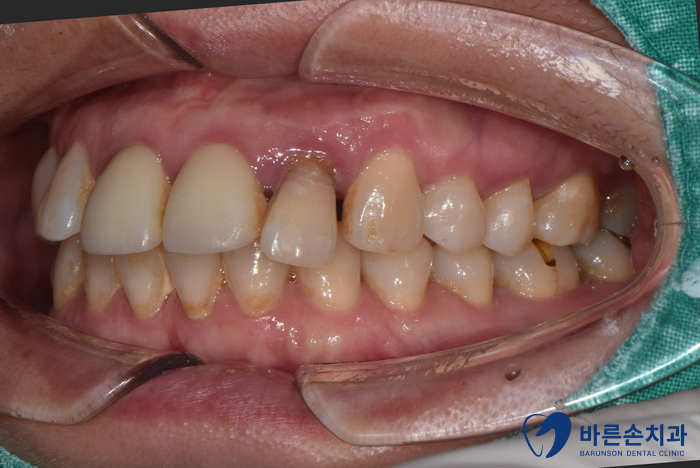

Before 25.05.08

보시면 앞니 하나가 유독 뼈가 내려가 있는 걸 볼 수 있어요.

치아를 잡아주는 뼈가 별로 없다보니

치아가 밑으로 내려오면서 많이 흔들리는 상태였습니다.ㅠㅠ

치아가 흔들리면 저작 시 움직이게 되어

통증을 느끼고 불편하십니다.

그래서 발치 후 임플란트로 치료계획을 세웁니다!